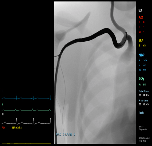

CORONARY INTERVENTION MODULE:

This module includes 10 virtual patient cases. The module provides significant experience in cardiac catheterization procedures (PTCA and stenting), including treatment of myocardiac infarction and complications such as dissections and perforations. Virtual patients vary in vasculature physiology and pathophysiology of the coronary circulation.

The module includes 2 bifurcation lesion cases in which kissing balloon technique is needed.